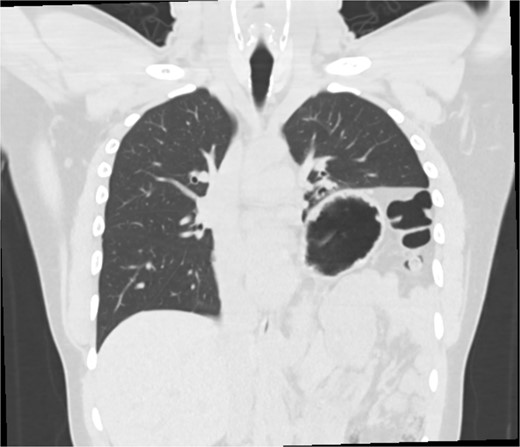

The early postoperative course was unremarkable. The patient reported feeling mild bloating, but was discharged on postoperative Day 1 after removal of a chest tube (Fig. 4). A few hours after discharge from the hospital, he developed dysphagia, progressive abdominal pain, distension, and dyspnea that prompted a return to the hospital. Physical examination revealed tachycardia (132 bpm), mild hypoxia requiring supplemental O2 at 2 L/min via nasal canula, and abdominal distension. Laboratory studies showed WBC of 12 600 cells/μL. A CT scan of the abdomen and pelvis revealed a large, acute organo-axial gastric volvulus without evidence of ischemia, and an intact left hemidiaphragm plication at a similar height to the right hemidiaphragm (Fig. 5). A nasogastric tube was placed with immediate drainage of 1 L of dark bilious fluid with immediate relief of the patient’s symptoms. However, a subsequent film revealed the nasogastric tube projecting toward the upper left chest with presence of colonic haustra (Fig. 6), consistent with acute hemidiaphragm rupture.

CT revealing intact diaphragm plication with massive organo-axial gastric volvulus.